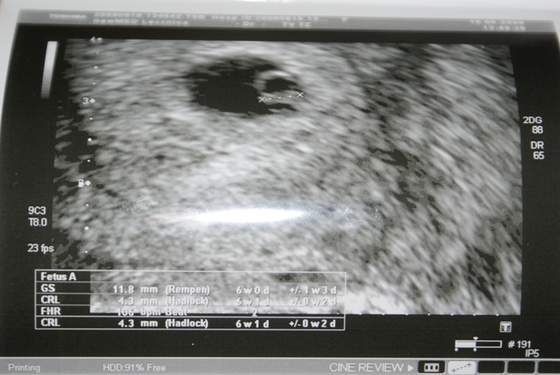

Dzisiaj byłam u ginka i ... moja druga Fasolka ma 4,3 mm i serduszko bije 106 razy na minutę. Mam cztery cudne zdjęcia i bez przerwy na nie patrzę.